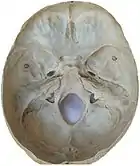

The human skull is anatomically divided into two parts: the neurocranium, formed by eight cranial bones that houses and protect the brain—and the facial skeleton (viscerocranium) composed of fourteen bones, not including the three ossicles of the inner ear.[22] The term skull fracture typically means fractures to the neurocranium, while fractures of the facial portion of the skull are facial fractures, or if the jaw is fractured, a mandibular fracture.[23]

The eight cranial bones are separated by sutures : one frontal bone, two parietal bones, two temporal bones, one occipital bone, one sphenoid bone, and one ethmoid bone.[24]

Skull fractures occur more easily at the thin squamous temporal and parietal bones, the sphenoid sinus, the foramen magnum (the opening at the base of the skull that the spinal cord passes through), the petrous temporal ridge, and the inner portions of the sphenoid wings at the base of the skull. The middle cranial fossa, a depression at the base of the cranial cavity forms the thinnest part of the skull and is thus the weakest part. This area of the cranial floor is weakened further by the presence of multiple foramina; as a result this section is at higher risk for basilar skull fractures to occur. Other areas more susceptible to fractures are the cribriform plate, the roof of orbits in the anterior cranial fossa, and the areas between the mastoid and dural sinuses in the posterior cranial fossa.[26]